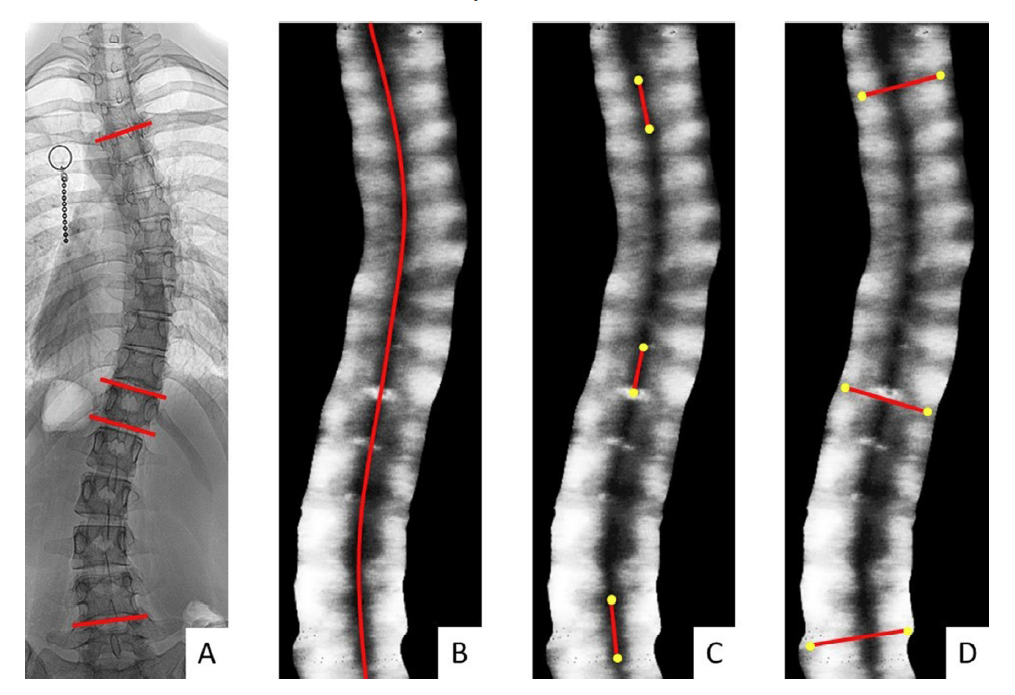

这项2018年的科研项目使用中心频率7.5 MHz、探头宽度7.5 cm的Scolioscan®SCN801设备进行扫描,Scolioscan®配套软件Scoliostudio从体投影图像中提取骨头特征,根据棘突阴影自动划线,测量出自动棘突角(下图B),手动棘突角(下图C)和手动横突角(下图D)则根据胸椎/腰椎的骨头阴影划出两条最倾斜的线再计算得出。33位患者包括男性和女性,他们脊柱侧弯的Cobb角范围在3°~90°之间。

A:冠状面Cobb角

B:自动棘突角

C:手动棘突角

D:手动横突角

Scoliostudio界面